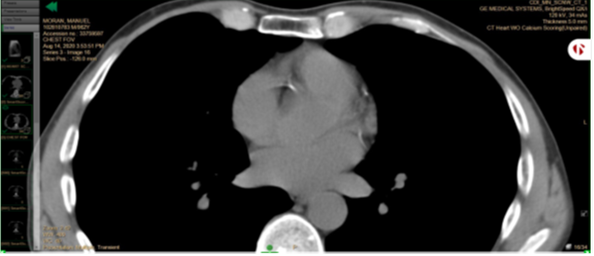

No cardiac events happened during the study period. The right coronary artery calcium score dropped from 39 in 2019 to 21 in 2020. Circumflex calcium score dropped from 9 to 2. In the CT images below, left upper cardiac artery is the right coronary artery; right lower artery is the circumflex.